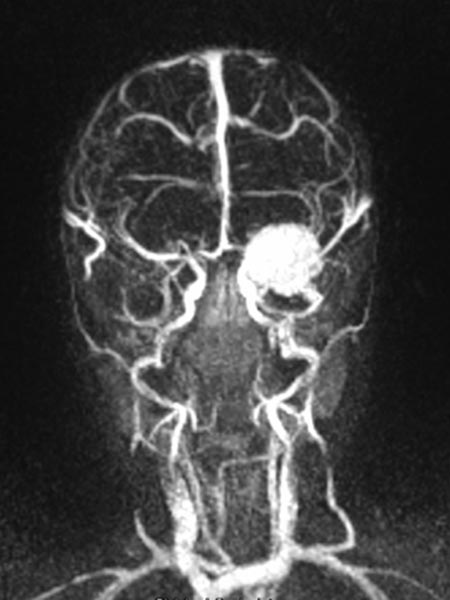

Dynamic contrast-enhanced MR angiography of the skull and cerebral vessels. In the very early arterial phase (A) no yet enhancement of the lesion in the left eye.

Dynamic contrast-enhanced MR-angiography in the arterial phase, 5 seconds later, depicts early and intense enhancement of the tumor in the left eye.

Dynamic, contrast-enhanced MR angiography, early venous phase. The strong enhancement remains, venous drainage via the facial veins and the left-sided external jugular vein.